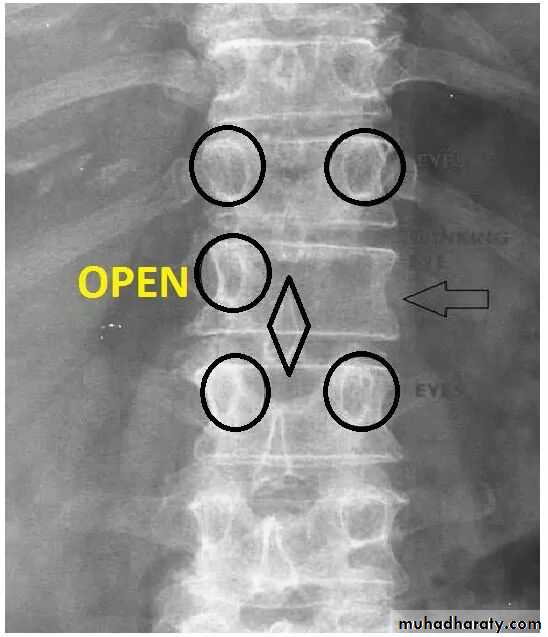

Winking Owl sign